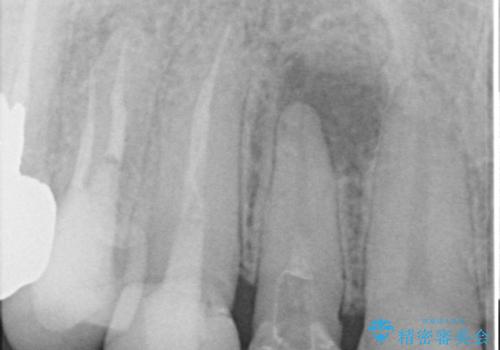

また、右上側切歯は根管治療が必要な状態でした。

右上側切歯に対して根管治療を行い、その後右上側切歯から左上犬歯まで計5本をオールセラミッククラウンで補綴する治療計画をご提案しました。